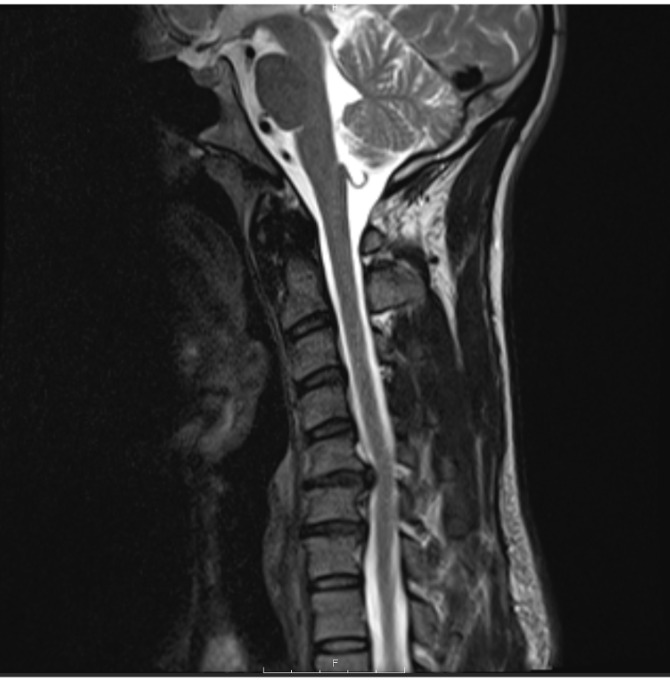

Case description: A 37-year-old male and Brazilian Jiu Jitsu athlete with cervical radiculopathy underwent a C5-C6 and C6-C7 discectomy with CTDR. The subject attended PT for 14 sessions across 16 weeks. Interventions included manual therapy (soft tissue and joint mobilization), therapeutic exercise targeting cervical spine, thoracic spine and upper extremity mobility and strength, and weightlifting body mechanics education. Radiographic confirmation of prosthesis placement and healing was monitored at postoperative weeks six and 12. The PT program was designed and progressed according to tissue healing timelines, subject response, clinical reasoning, and sport-specific demands.